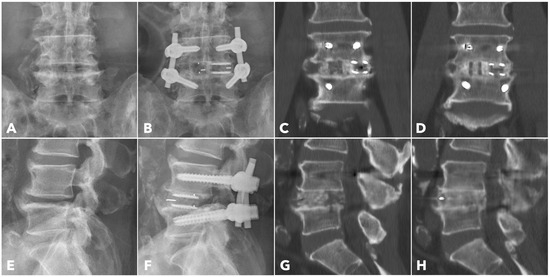

Improved Clinical and Radiological Outcomes with Double-Cage Biportal Endoscopic Transforaminal Lumbar Interbody Fusion: A Comparative CT-Based Study

by Yu-Hao Huang and Jwo-Luen Pao

Diagnostics 2025, 15(20), 2652; https://doi.org/10.3390/diagnostics15202652 - 21 Oct 2025

Cited by 1 | Viewed by 1504

Abstract

Background/Objectives: When transitioning from an older surgical technique to a newer one, we expect improved treatment outcomes and fewer complications. However, direct comparative studies to confirm these advantages are often lacking. Tubular minimally invasive transforaminal lumbar interbody fusion (MISTLIF) has been widely [...] Read more.

Background/Objectives: When transitioning from an older surgical technique to a newer one, we expect improved treatment outcomes and fewer complications. However, direct comparative studies to confirm these advantages are often lacking. Tubular minimally invasive transforaminal lumbar interbody fusion (MISTLIF) has been widely used, but limitations in visualization and endplate preparation may compromise fusion quality. Biportal endoscopic TLIF (BETLIF), a more recent alternative, offers enhanced magnification and superior hemostasis. Still, CT-based comparative data on fusion integrity remain limited. To evaluate the clinical and radiological outcomes following a chronological transition from MISTLIF to BETLIF, using thin-slice CT to assess fusion integrity. Methods: This retrospective study analyzed 179 patients treated by a single surgeon between January 2018 and May 2021. The first 90 cases underwent MISTLIF, followed by 89 BETLIF procedures. Clinical outcomes included Visual Analog Scale (VAS), Oswestry Disability Index (ODI), and Japanese Orthopedic Association (JOA) scores. Radiological assessments at one year postoperatively (X-ray and thin-slice CT) included disc height, segmental lordosis, Bridwell fusion grade, cage subsidence, and subchondral osteolysis. Results: BETLIF was associated with significantly shorter hospital stays (5.7 vs. 7.4 days) and fewer transfusions (0% vs. 14.7%). BETLIF showed significantly better ODI (12.7 vs. 23.5), JOA scores (26.4 vs. 20.6), and comparable VAS improvement. Radiologically, BETLIF had significantly higher fusion rates (93.3% vs. 82.4%), greater disc height restoration, and lower rates of cage subsidence (5.0% vs. 13.7%) and osteolysis (13.3% vs. 52.9%). Conclusions: BETLIF demonstrated superior clinical and radiological outcomes, likely due to enhanced endoscopic visualization and precise endplate preparation. Full article

(This article belongs to the Special Issue Diagnosis and Management of Spinal Diseases)

Show Figures

Figure 1